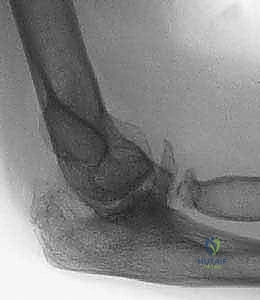

FIG 2 • AP and lateral radiographs of the elbow in a patient with posttraumatic arthritis of the elbow.

- Radiographs: Orthogonal radiographic views (AP and lateral) of the elbow are mandatory.

- Oblique Radiographs: These can be very helpful in obtaining more detailed views of specific areas, especially for subtle fractures or osteophytes.

- Lateral Radiograph: Typically, a good lateral radiograph is relatively easy to obtain.

- Anteroposterior (AP) Radiograph: A useful AP radiograph can be challenging, particularly if the patient presents with a significant flexion contracture. A poorly positioned AP radiograph can make accurate assessment of the joint space difficult, often leading to an overestimation of the amount of joint destruction.